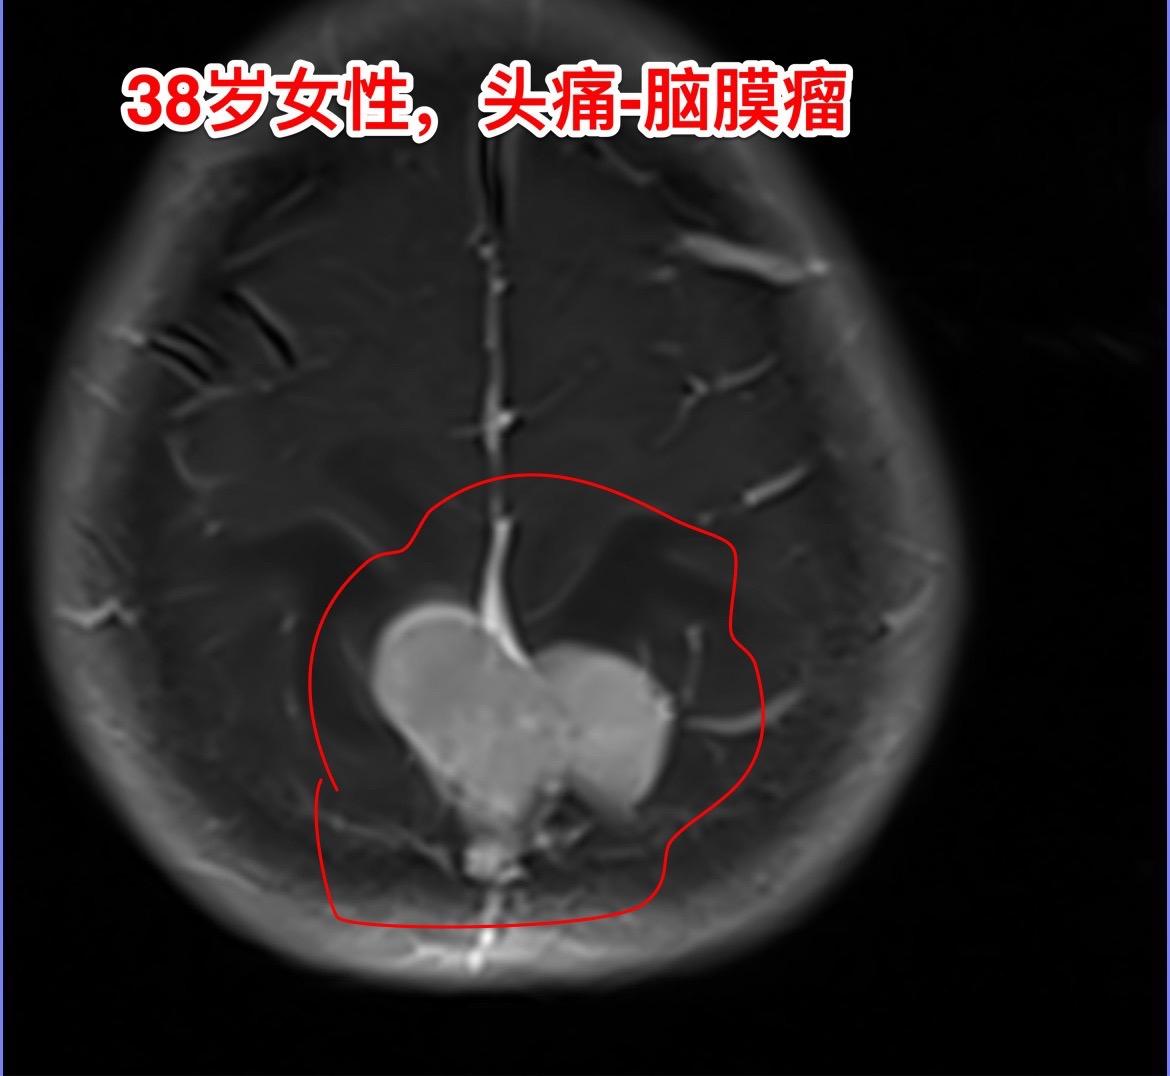

脑膜瘤的病理诊断—-需要格外关注。绝大多数的脑膜瘤都是良性肿瘤,小部分脑膜瘤是非典型的,也有一部分脑膜瘤呈恶性。 这个38岁湖北女性,因为头痛发现脑膜瘤。磁共振显示脑膜瘤周围有大范围的脑水肿,手术过程中发现肿瘤侵蚀了颅骨,将颅骨吃透了。直观的感受是:这个脑膜瘤是不是呈恶性趋势? 病理报告这个脑膜瘤是WHO1级,是良性肿瘤。只是Ki67指标稍高,以后需要定期复查。 这个病人手术后没有出现下肢活动无力症状,很快就能下地活动。这个位置的手术比颅咽管瘤手术要轻松许多,